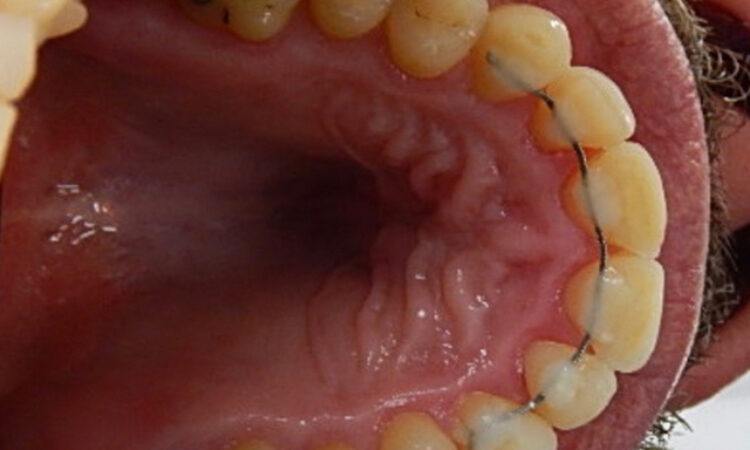

Before - puredental After - puredental

Case 19 - Invisalign®